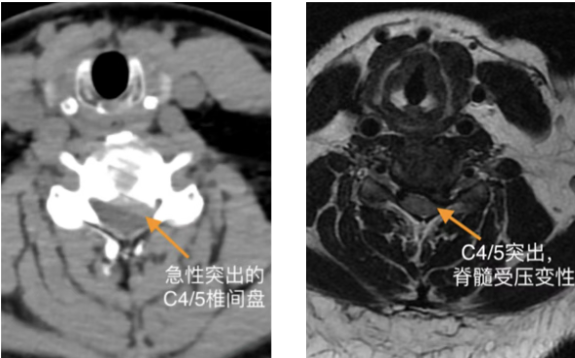

随后,患者相继出现头晕、头痛、呕吐及会阴区麻木。医疗团队紧急启动预案,查CT与MRI结果排除脑出血与急性脑梗死,最终确诊为颈3/4、颈4/5椎间盘突出压迫脊髓,伴脊髓部分变性,解除脊髓压迫为治疗关键。

面对紧急的病情,副院长、脊柱外科主任李世芳带领团队迅速评估,决定采用目前脊柱内镜微创技术——Endo-ACDF(内镜下前路颈椎间盘切除融合术),实施了C3/4、C4/5节段的内镜下减压融合手术。该技术通过天然颈前间隙建立微小通道,在水介质下通过内镜放大视野,能够精准地切除压迫脊髓的突出椎间盘,并植入椎间融合器稳定颈椎。其优势在于创伤极小,出血极少,能最大程度保护周围正常组织结构。